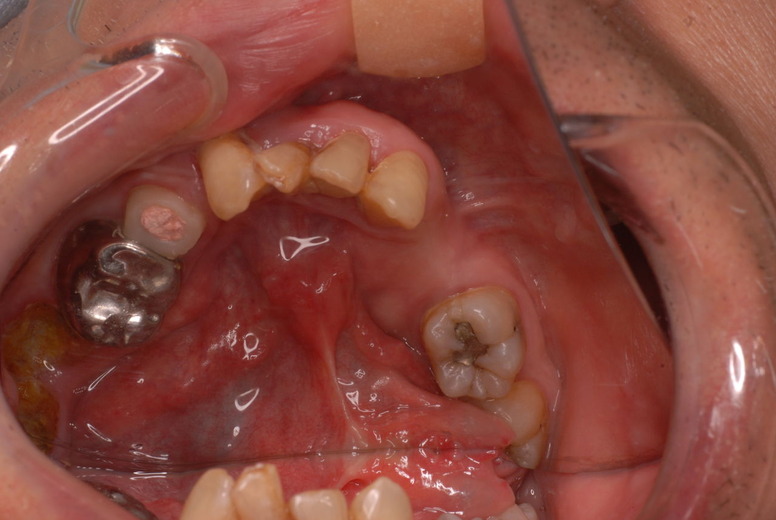

写真左下の親知らずが痛くなり抜歯しました。その後歯茎を除去して虫歯を露出させる処置を二回ほどしています。

レントゲンでは小さいですが、こう言う虫歯が一番怖いのです。

治療の成功率は極めて悪くすぐ再発しやすいのです。